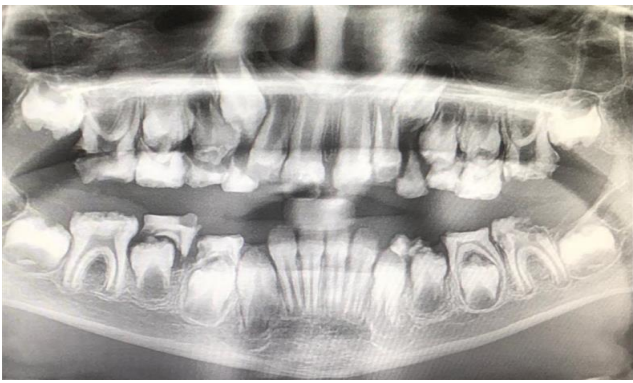

Oral (figure 1) and radiographic (figure 2) examination of the patient showed consistent dental findings: generalized, thin hypoplastic or absent enamel; both primary and permanent teeth affected; flat cusps on posterior teeth; relative microdontia and spaced teeth; delayed tooth eruption; impacted posterior teeth; and semi-lunar shape of central incisor edge. Hypomaturation or hypocalcified AI have never been described in ERS.1

Figure 2: Radiographic examination